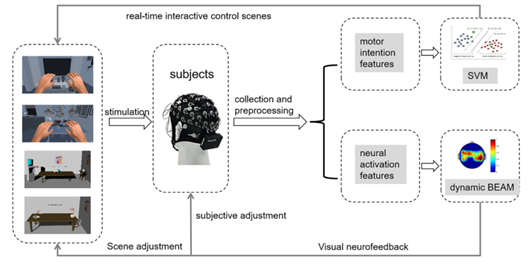

图1 基于MI-BCI和VR的虚拟康复策略图

如图1所示,我们设计了基于MI-BCI和VR的康复训练策略。多个诱发MI刺激场景(例如,静态场景、动态场景和VR场景)诱导受试者执行MI任务,并实时采集EEG信号。接下来对EEG信号进行预处理,再进行双分支的输出和反馈。第一分支,运动想象分类识别(运动意识特征提取&SVM分类)。我们将虚拟左手和右手的图像添加到场景中,并设置训练任务和视听反馈,引导受试者进行主动MI任务。通过人机交互控制,受试者可以感觉到他们正在进行实际的身体动作。第二分支,神经激活程度分析(神经激活特征提取&动态脑电活动图)。我们通过脑电活动图观察大脑区域的激活变化,并分析训练对受试者的影响。根据大脑运动区的当前神经活动,我们自适应调整训练场景,以确保受试者能够持续实现神经的最大激活,并加速神经功能的重塑。